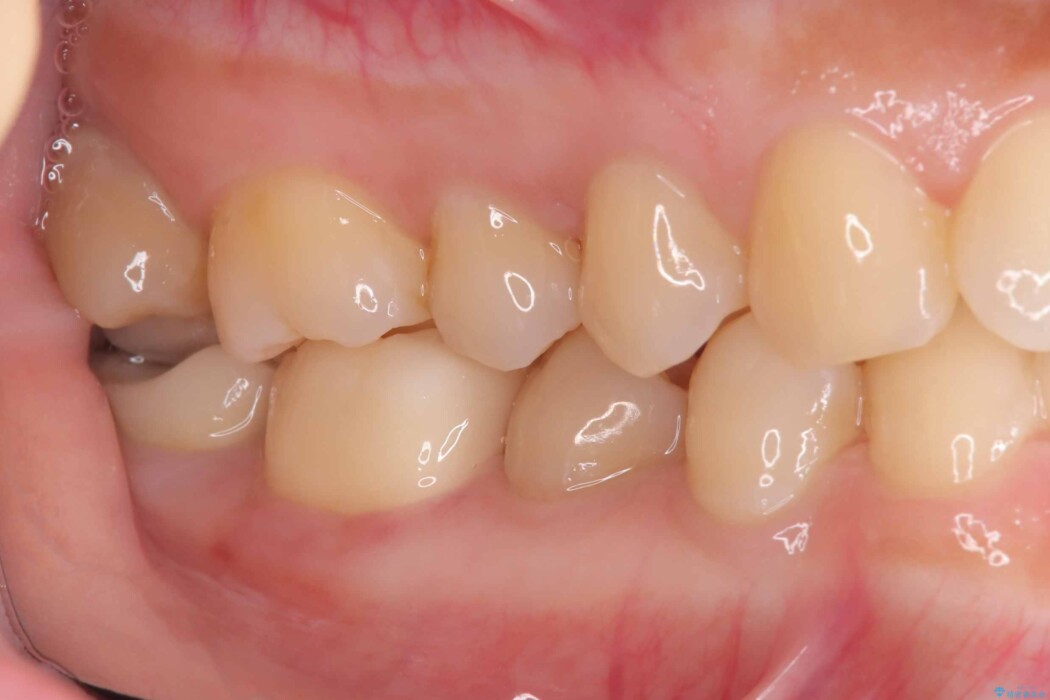

歯と歯の間に虫歯があった患者様です。

噛む面や外側にも過去の詰め物が入っている状態で、このように詰め物の範囲が大きいと治療後に歯が割れてしまうリスクが高くなります。

今回は歯の強度と将来的な破折リスクを考慮し、セラミッククラウンによる治療を行うこととしました。